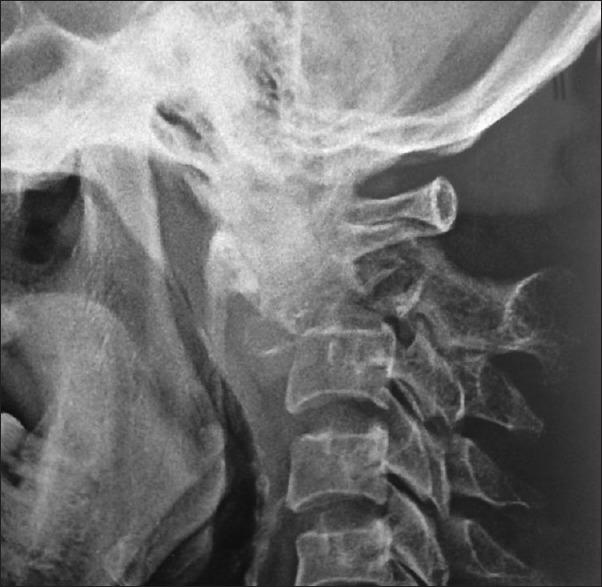

Clinical case report and review of the literature. This is the first case of primary leiomyoma in an immunocompetent woman without previous history of uterine leiomyoma being reported in the literature to the best of our knowledge. Leiomyoma, a type of smooth muscle cell tumor, involving the vertebra is extremely rare. There were very few primary leiomyoma in patients with AIDS or in the immune-suppressed patients. This 48-year-old female came with H/o neck pain, weakness and bladder retention. On examination, tone increased in all four limbs, power on the right side of the limbs 4/5, power on the left upper limb 0/5, lower limb 3/5, left plantar was up going, decreased sensation over the left second cervical vertebra (C2) dermatome and all modalities decreased below C2. X-ray and magnetic resonance imaging (MRI) of the cervical spine showed kyphosis of the cervical spine with destruction of the C2 vertebral body along with pathological fracture. The patient underwent decompression of the C2 lesion through the C2 right pedicle with occipito-C1-C3 lateral mass screws fixation. Lesion anterior to the cord was reached by a transpedicular approach and decompression was performed. The lesion was pinkish grey, firm and moderately vascular and was destroying the C2 vertebral body. The patient improved symptomatically in power in the left upper limb and lower limb over the next 1 week duration from 0/5 to 4+/5. Histopathology revealed primary leiomyoma. The patient was evaluated with ultrasound abdomen and contrast tomogram of the chest, abdomen and pelvis to rule out other possible lesions in the lung, intestines and uterus. We suggest that leiomyoma should be included in the differential diagnosis of destructive lytic lesions involving the C2 vertebra. Histopathological examination with immunohistochemistry is necessary for the definitive diagnosis. Treatment of choice is surgery with complete removal.